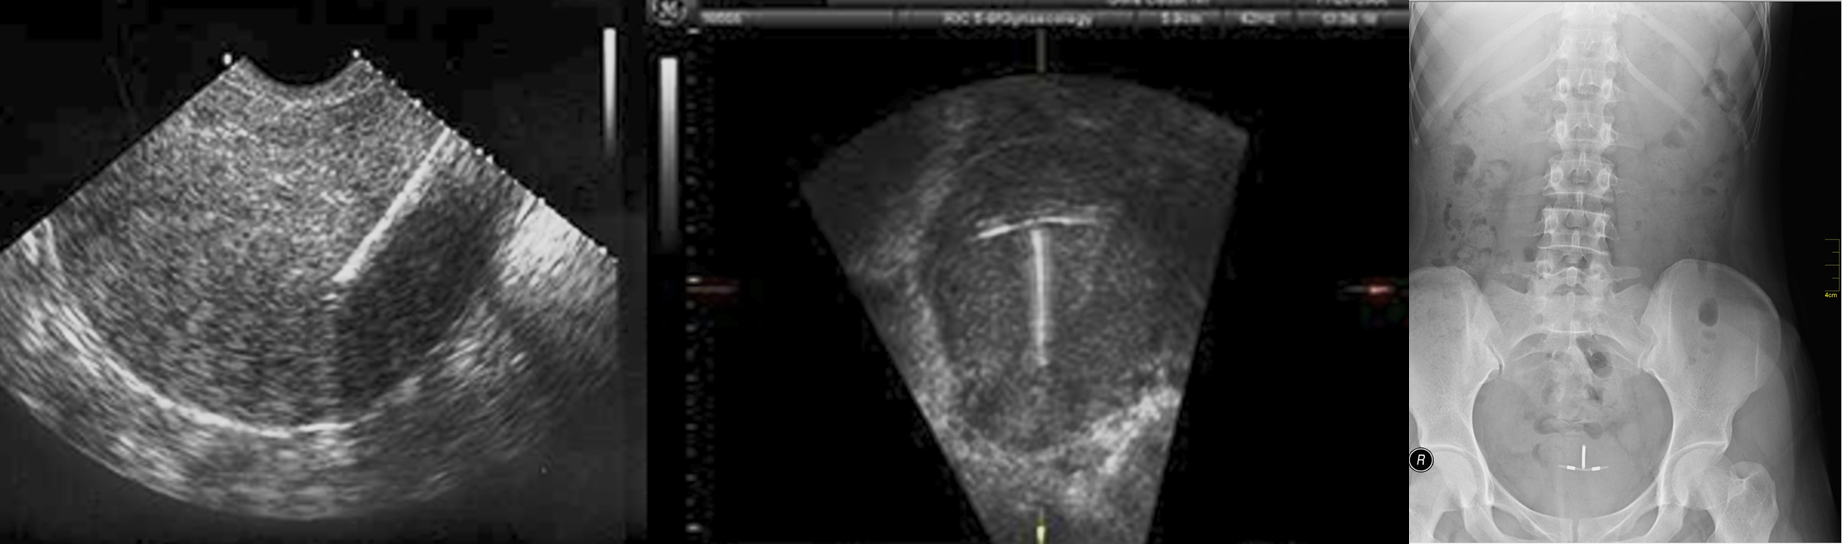

The lost intrauterine contraceptive device (IUCD) is a relatively common problem and ultrasound should be the first investigation

They are seen as highly reflective structures and their relationship to the uterine cavity can be determine.

If the IUCD cannot be located in the pelvis, then a plain film of the abdomen should be taken in case the device has migrated through the uterus.

longitudinal ultrasound scan.

Intrauterine contraceptive device seen as a linear reflective echo within the uterine cavity